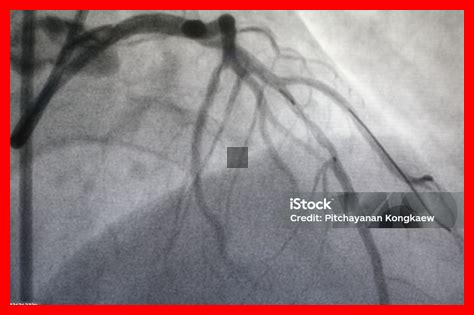

Les rayons X sont principalement utilisés dans deux types d’examens : la radiographie thoracique et l’angiographie. La radiographie thoracique permet de détecter des anomalies telles que l’élargissement du cœur ou la présence de liquide dans les poumons, souvent indicatif d’une insuffisance cardiaque. D’autre part, l’angiographie par rayons X, qui utilise un agent de contraste, permet de visualiser les artères coronaires et d’identifier d’éventuelles obstructions.